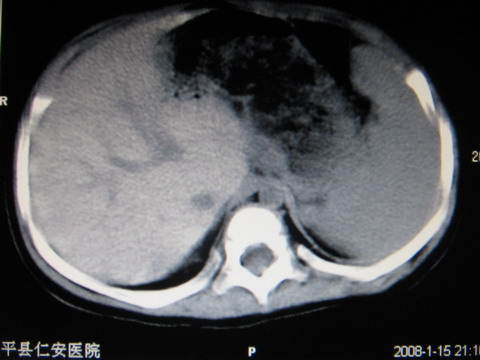

标题: PED0552:男1岁,双肾区CT

胎龄5个月时b超示左肾积水,现一岁后复查

左肾重度积水!

左肾重度积水!考虑肾盂输尿管交界处先天性狭窄或闭塞所导致

左肾重度积水.

左肾重度积水。

左肾重度积水(先天性左输尿管狭窄所致?)。

先天性左输尿管狭窄所致左肾重度积水。